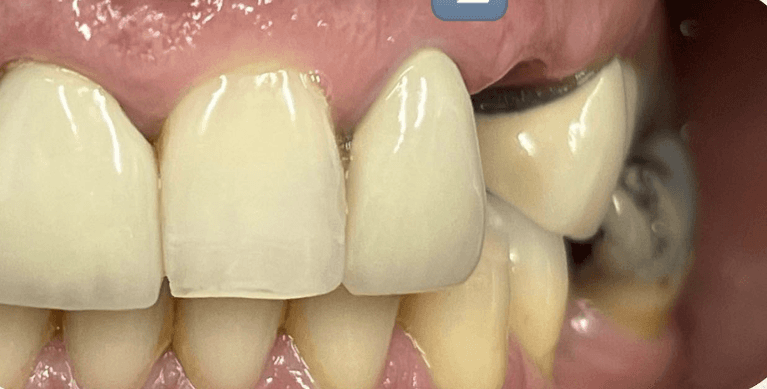

Smiles are always in fashion because the prettiest thing you can wear is a smile (maybe mask for a time being ) Before and after pictures of 4 porcelain veneers.

Smiles are always in fashion because the prettiest thing you can wear is a smile (maybe mask nowadays) Before and after pictures of yesterday’s case. Slight gum bleeding was from flossing..no biggie